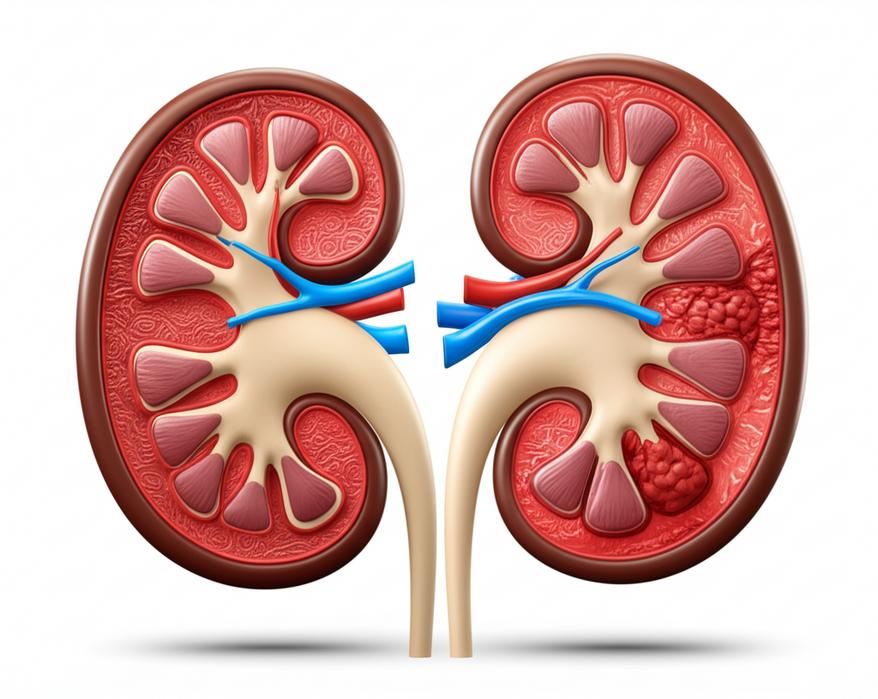

ไตทั้งสองข้างของเราเปรียบเสมือนโรงงานกรองขนาดเล็กที่ทำงานตลอด 24 ชั่วโมงเพื่อรักษาความสะอาดและสมดุลภายในร่างกาย หน้าที่หลักของไตคือการกรองของเสีย สารพิษ และน้ำส่วนเกินออกจากเลือด เพื่อขับถ่ายออกทางปัสสาวะ นอกจากนี้ ไตยังมีบทบาทสำคัญในการควบคุมความดันโลหิต สร้างเม็ดเลือดแดง และรักษาสมดุลของอิเล็กโทรไลต์และกรด-ด่างในร่างกายอีกด้วย

อย่างไรก็ตาม เมื่อเวลาผ่านไป ด้วยปัจจัยหลายประการ ไตก็สามารถเสื่อมสภาพลงได้ กลไกการเสื่อมของไตมักเกี่ยวข้องกับการอักเสบเรื้อรัง (Chronic Inflammation) และภาวะเครียดออกซิเดชัน (Oxidative Stress) ซึ่งเป็นผลมาจากการสะสมของสารพิษในร่างกาย การทานอาหารที่ไม่เหมาะสม และการขาดสารอาหารบางชนิด สิ่งเหล่านี้ส่งผลให้หน่วยกรองของไต (Nephrons) ถูกทำลายลงอย่างช้าๆ และสูญเสียความสามารถในการทำงาน ไตที่เสื่อมสภาพมักจะแสดงอาการที่ละเอียดอ่อนในระยะแรก ซึ่งทำให้หลายคนไม่ทันสังเกต และเมื่ออาการปรากฏชัดเจน มักจะหมายถึงไตได้ถูกทำลายไปแล้วเป็นจำนวนมาก